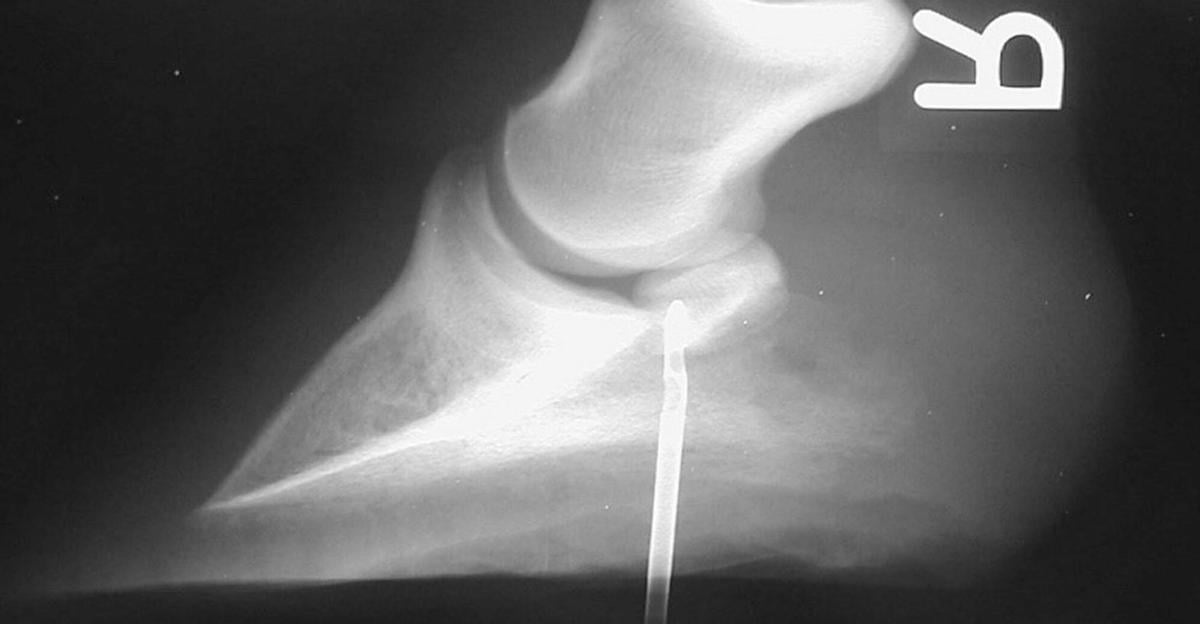

Nail Puncture Wound In Horses Foot Nail Ftempo

Nail Puncture Wound In Horses Foot Nail Ftempo Horse Hoof Puncture Wound Treatment Shoes with splints to help with tendon. treating an abscess or superficial penetration injury is quite simple and involves applying a foot poultice. a puncture wound to the hoof is an extremely common injury in horses and is always considered an emergency. puncture wounds from nails or other objects are in a whole different category and need. Horse Hoof Puncture Wound Treatment.

Luke Puncture Wound from a Nail in the Foot — Burwash Equine Services Horse Hoof Puncture Wound Treatment a puncture wound to the hoof is an extremely common injury in horses and is always considered an emergency. treating an abscess or superficial penetration injury is quite simple and involves applying a foot poultice. Shoes with splints to help with tendon. If no critical structures have been damaged, treatment is. puncture wounds from nails or other. Horse Hoof Puncture Wound Treatment.